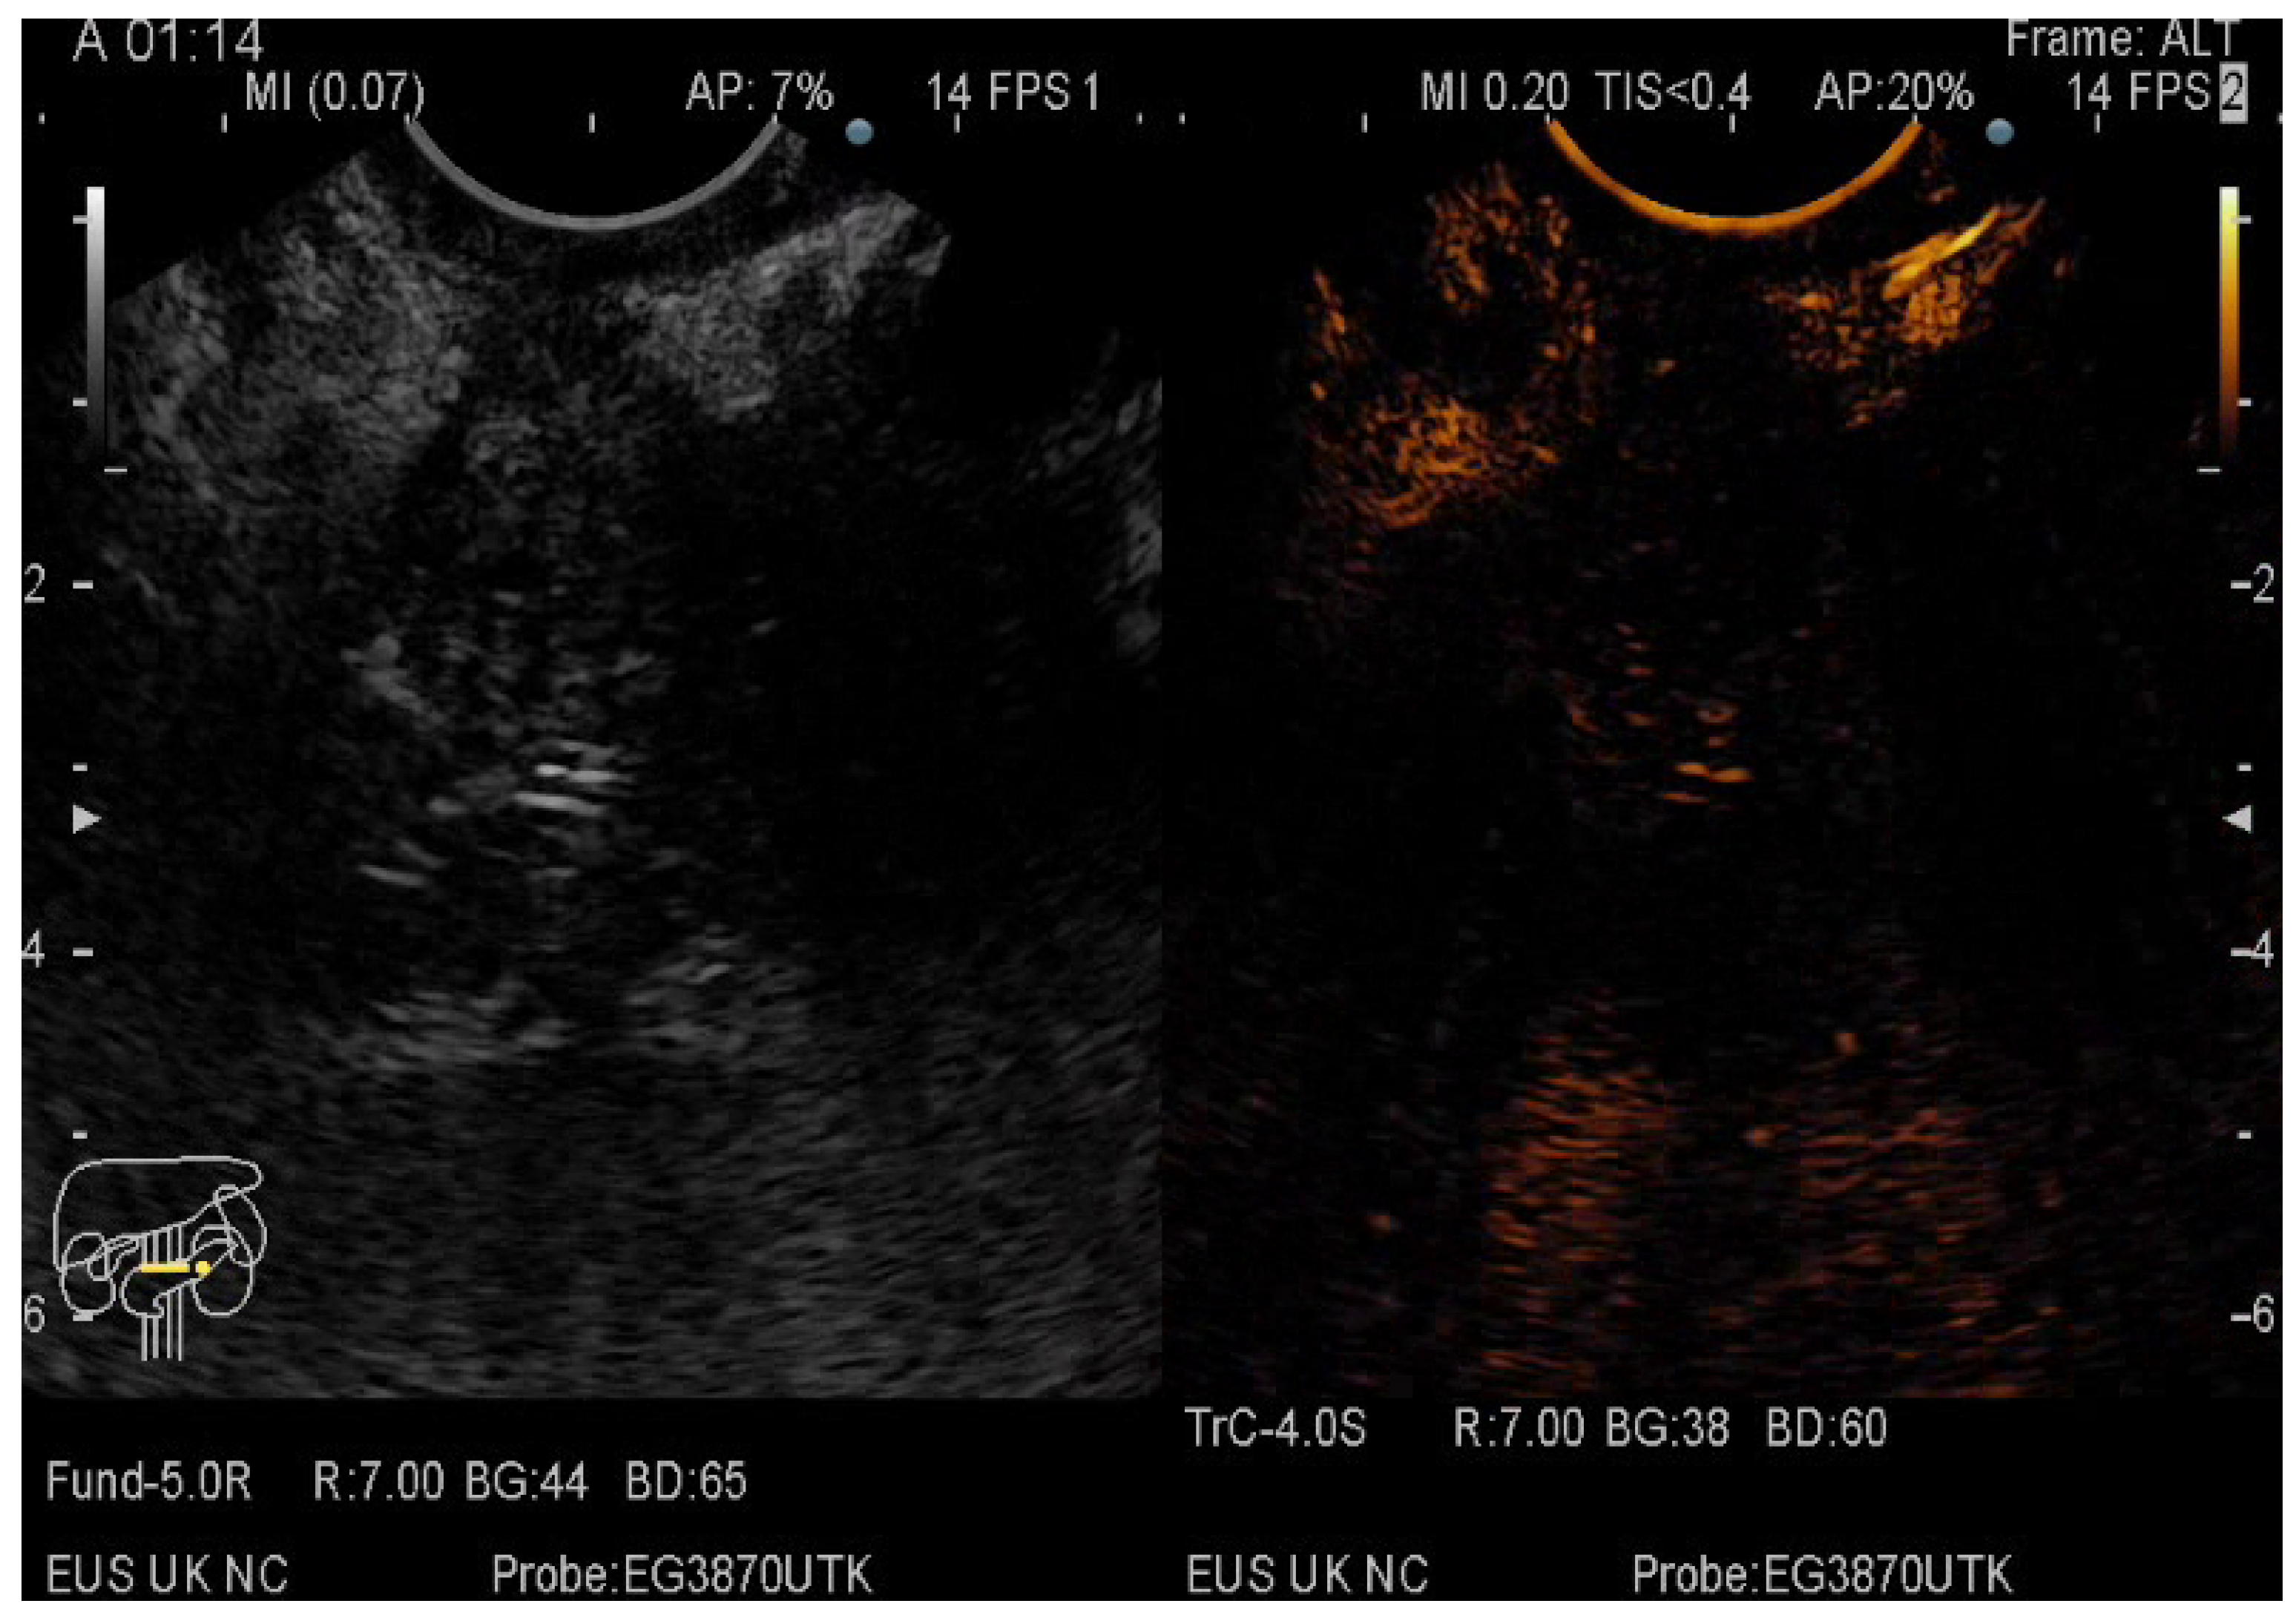

The pancreatic masses where located as it follows: 2/3 at the head level and 1/3 at the level of the body and tail. The size of the pancreatic masses ranged from 10 to 78 mm, with an average diameter of 35 mm. For obtaining the core tissue, fanning technique was applied with a mean number of needle passes of 2 and a range from 2 to 5 passes. Final pathology revealed pancreatic ductal adenocarcinoma–PDAC (149) (Figure 3), mass-forming pancreatitis–MFP (57) (Figure 4), pancreatic neuroendocrine tumors–pNETs (23) (Figure 5 and Figure 6), undifferentiated carcinoma (17), mucinous carcinoma (5), and pancreatic metastasis (5).

Figure 3.

CE-EUS image of a PDAC showing a hypoenhancing solid mass in both arterial and venous phase.

In 48% of the cases, the pancreatic lesion was described as hypoenhancing, with a final diagnosis of malignancy. Regarding the enhancement patterns, hypovascularity in both arterial and venous phase was associated with PDAC, hypervascularity or isovascularity in both phases were associated with either MFP or NETs, whereas the carcinomas were hypervascular (Table 6). A heterogeneous appearance with non-enhancing areas was noted in a small percentage of the hypoenhancing lesions and it might suggest necrosis. The overall diagnostic accuracy was 91%.